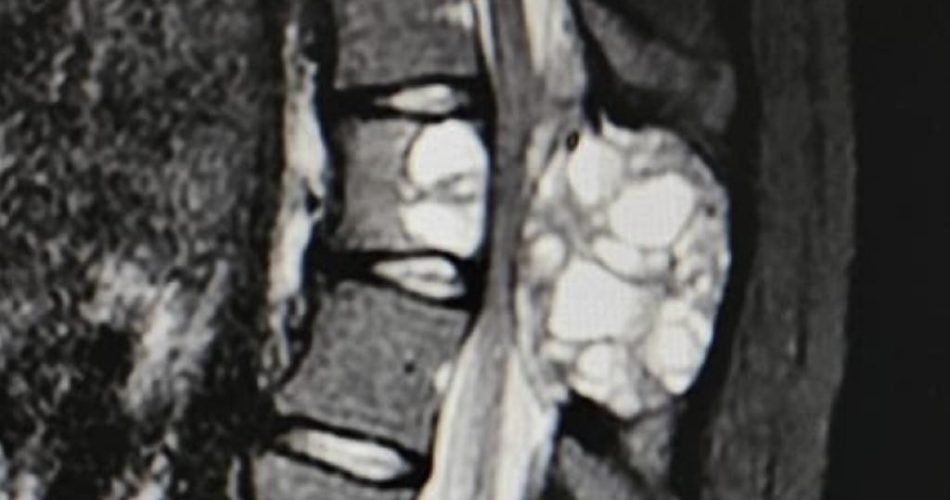

la cisti aneurismatica vertebrale

Una rara cisti aneurismatica vertebrale che avrebbe potuto comportare deficit midollari è stata diagnosticata e rimossa al Policlinico di Bari su una quindicenne. Il mal di schiena cronico impediva alla ragazza di svolgere la sua vita. Tante visite nessuna soluzione, il trasferimento con la famiglia da Como a Bari e la visita in ortopedia dal prof. Biagio Moretti, direttore dell’unità operativa. La risonanza magnetica del rachide ad alto campo ha permesso di togliere ogni dubbio.

“Anche se si tratta di una forma di neoplasia benigna, la cisti aneurismatica vertebrale in quei rari casi in cui interessa sia il corpo vertebrale che l’arco posteriore, può anche dare deficit midollari. All’ingresso la ragazza era neurologicanente asintomatica ma sapevamo che da un momento all’altro tutto sarebbe potuto cambiare”, spiega il dottor Andrea Piazzolla, responsabile della unità operativa di Chirurgia Vertebrale che ha preso in carico il caso.